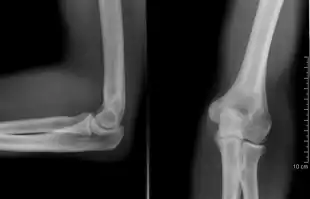

Projectional radiography

The creation of images by exposing an object to X-rays or other high-energy forms of electromagnetic radiation and capturing the resulting remnant beam (or "shadow") as a latent image is known as "projection radiography." The "shadow" may be converted to light using a fluorescent screen, which is then captured on photographic film, it may be captured by a phosphor screen to be "read" later by a laser (CR), or it may directly activate a matrix of solid-state detectors (DR—similar to a very large version of a CCD in a digital camera). Bone and some organs (such as lungs) especially lend themselves to projection radiography. It is a relatively low-cost investigation with a high diagnostic yield. The difference between soft and hard body parts stems mostly from the fact that carbon has a very low X-ray cross section compared to calcium.